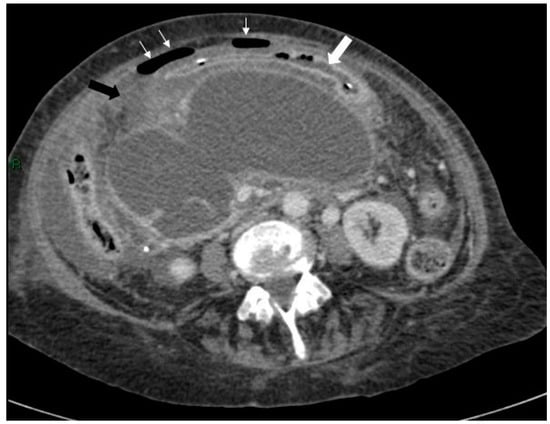

A 72-year-old female attended for a laparoscopic cholecystectomy on the background of severe gallstone pancreatitis four weeks previously. Examination prior to her operation revealed that she had an upper abdominal mass. The procedure was cancelled, and computed tomography (CT) was performed. This revealed a pseudocyst with three components—a large 16 × 12 cm thin-walled cyst in relation to the head, body and proximal tail of the pancreas, a separate 6 cm cyst in the distal tail, and a 10 × 5 cm cyst in the area of the transverse mesocolon compressing the transverse colon (Figure 1 and Figure 2).

Figure 1.

Axial post-contrast computed tomography (CT) scan of the upper abdomen showing a large pancreatic pseudocyst with the stomach (arrows) stretched anteriorly over it.